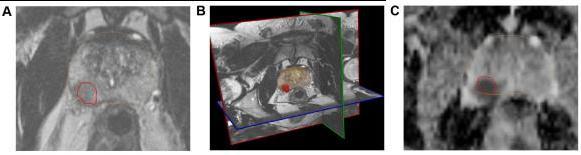

T2-weighted imaging assessment. High-resolution axial, sagittal, and coronal T2-weighted imaging (T2WI) sequences showprostatezonalanatomyandsofttissuecontrast(Fig.4B).T2WIcanbestdetectzonalanatomicalanomaliesinPCacells (or to depict seminal vesicle invasion and extracapsular extension of disease). Normal PZtissueiswater-richwithmany ductalandacinarcomponentsandsparselyinterlacedsmoothmuscle.T2-weighted picturesshowitasbright.PCainthePZ showsasaroundedorill-definedlow-signalintensityfocus(Fig.4A),unlikethelooselypackedtypicalPZtissue.Prostatitis, atrophy,andpreviousbiopsy-relatedhaemorrhagescanmimicalow-signalintensityfocusinthePZofT2-weightedimages. On T2WI, normalTZ tissuelooksdarkerthanthePZdue to its lower watercontent,compact smooth muscle,and sparser glandularcomponents.PCaintheTZappearsasauniform,low-signalmasswithfuzzyborders.Duetoitslargemuscleand fibrouscontent,theTZmaylooklow-signalintensity,makingitdifficulttoidentifycancerfromstromalBPH.[24]DWI.PCa has dense tumor cell areas. The high intracellular/extracellular volume ratio of these locations limits water molecule Brownianmotionintheextracellularspace.DWIdetectswatermolecules'randomBrownianmotion.Changingmagneticfield durationand strength yields two or more DWI pictures (indicated by a b-value). Cancer appears bright hyperintense on DW imaging because restricted water diffusion reduces signal loss. Cancers appear as hypointense dark spots on an Apparent DiffusionCoefficient(ADC) mapmadefromnumerousb-valueDWimages(Fig.4C).ADCreadingspredict cancer aggressiveness.Ultra-highb-valueDWI(e.g.,2000seconds/mm2;Fig.4D)mayimproveindexlesiondetermination.

Fig – 4 : The mpMRI depiction of right posterolateral lesion: (A) axial T2-weighted image with lesion inred outline, (B) 3D T2-weighted view of prostate contour (brown) and lesion (red), (C) ADC image with lesion in red outline, (D) computed high b-value = 2000 seconds/mm2 image with lesion in red outline, (E) dynamic contrast-enhanced pharmacokinetic map with lesion in red outline, (F) average time–signal intensity curve plot of the lesion, and (G) PIRADS version 2 location of lesion (orange). Dynamic contrast-enhanced imaging. DCE-MRI uses 3D T1-weighted images before, during, and after intravenous contrast media injection (typically low-molecular-weight Gadolinium chelates that rapidly diffuse in extravascular extracellular space). As said, aggressive tumors produce angiogenic agents that stimulate microvessel proliferation. New microvesselsaredisorderedandleakyduetoweakenedwalls.TumorangiogenesiscausesearlyDCE-MRenhancementinPCa tissue.TheDCE-MRimagesareusuallyanalyzedforlesions(a)qualitatively,byvisual inspection of subtraction time points forpotentiallycancerousspotsshowingfocalenhancement;(b)semiquantitatively,bytime–signalintensitycurveanalysis (Fig. 4F) of suspicious voxels to determine parameters like time-to-peak,wash-inslope, etc.; and/or(c) quantitatively,by compartmentalpharmacokineticmodellingthatusescontrastmediaconcentrationandotherparameters(Fig.4E).